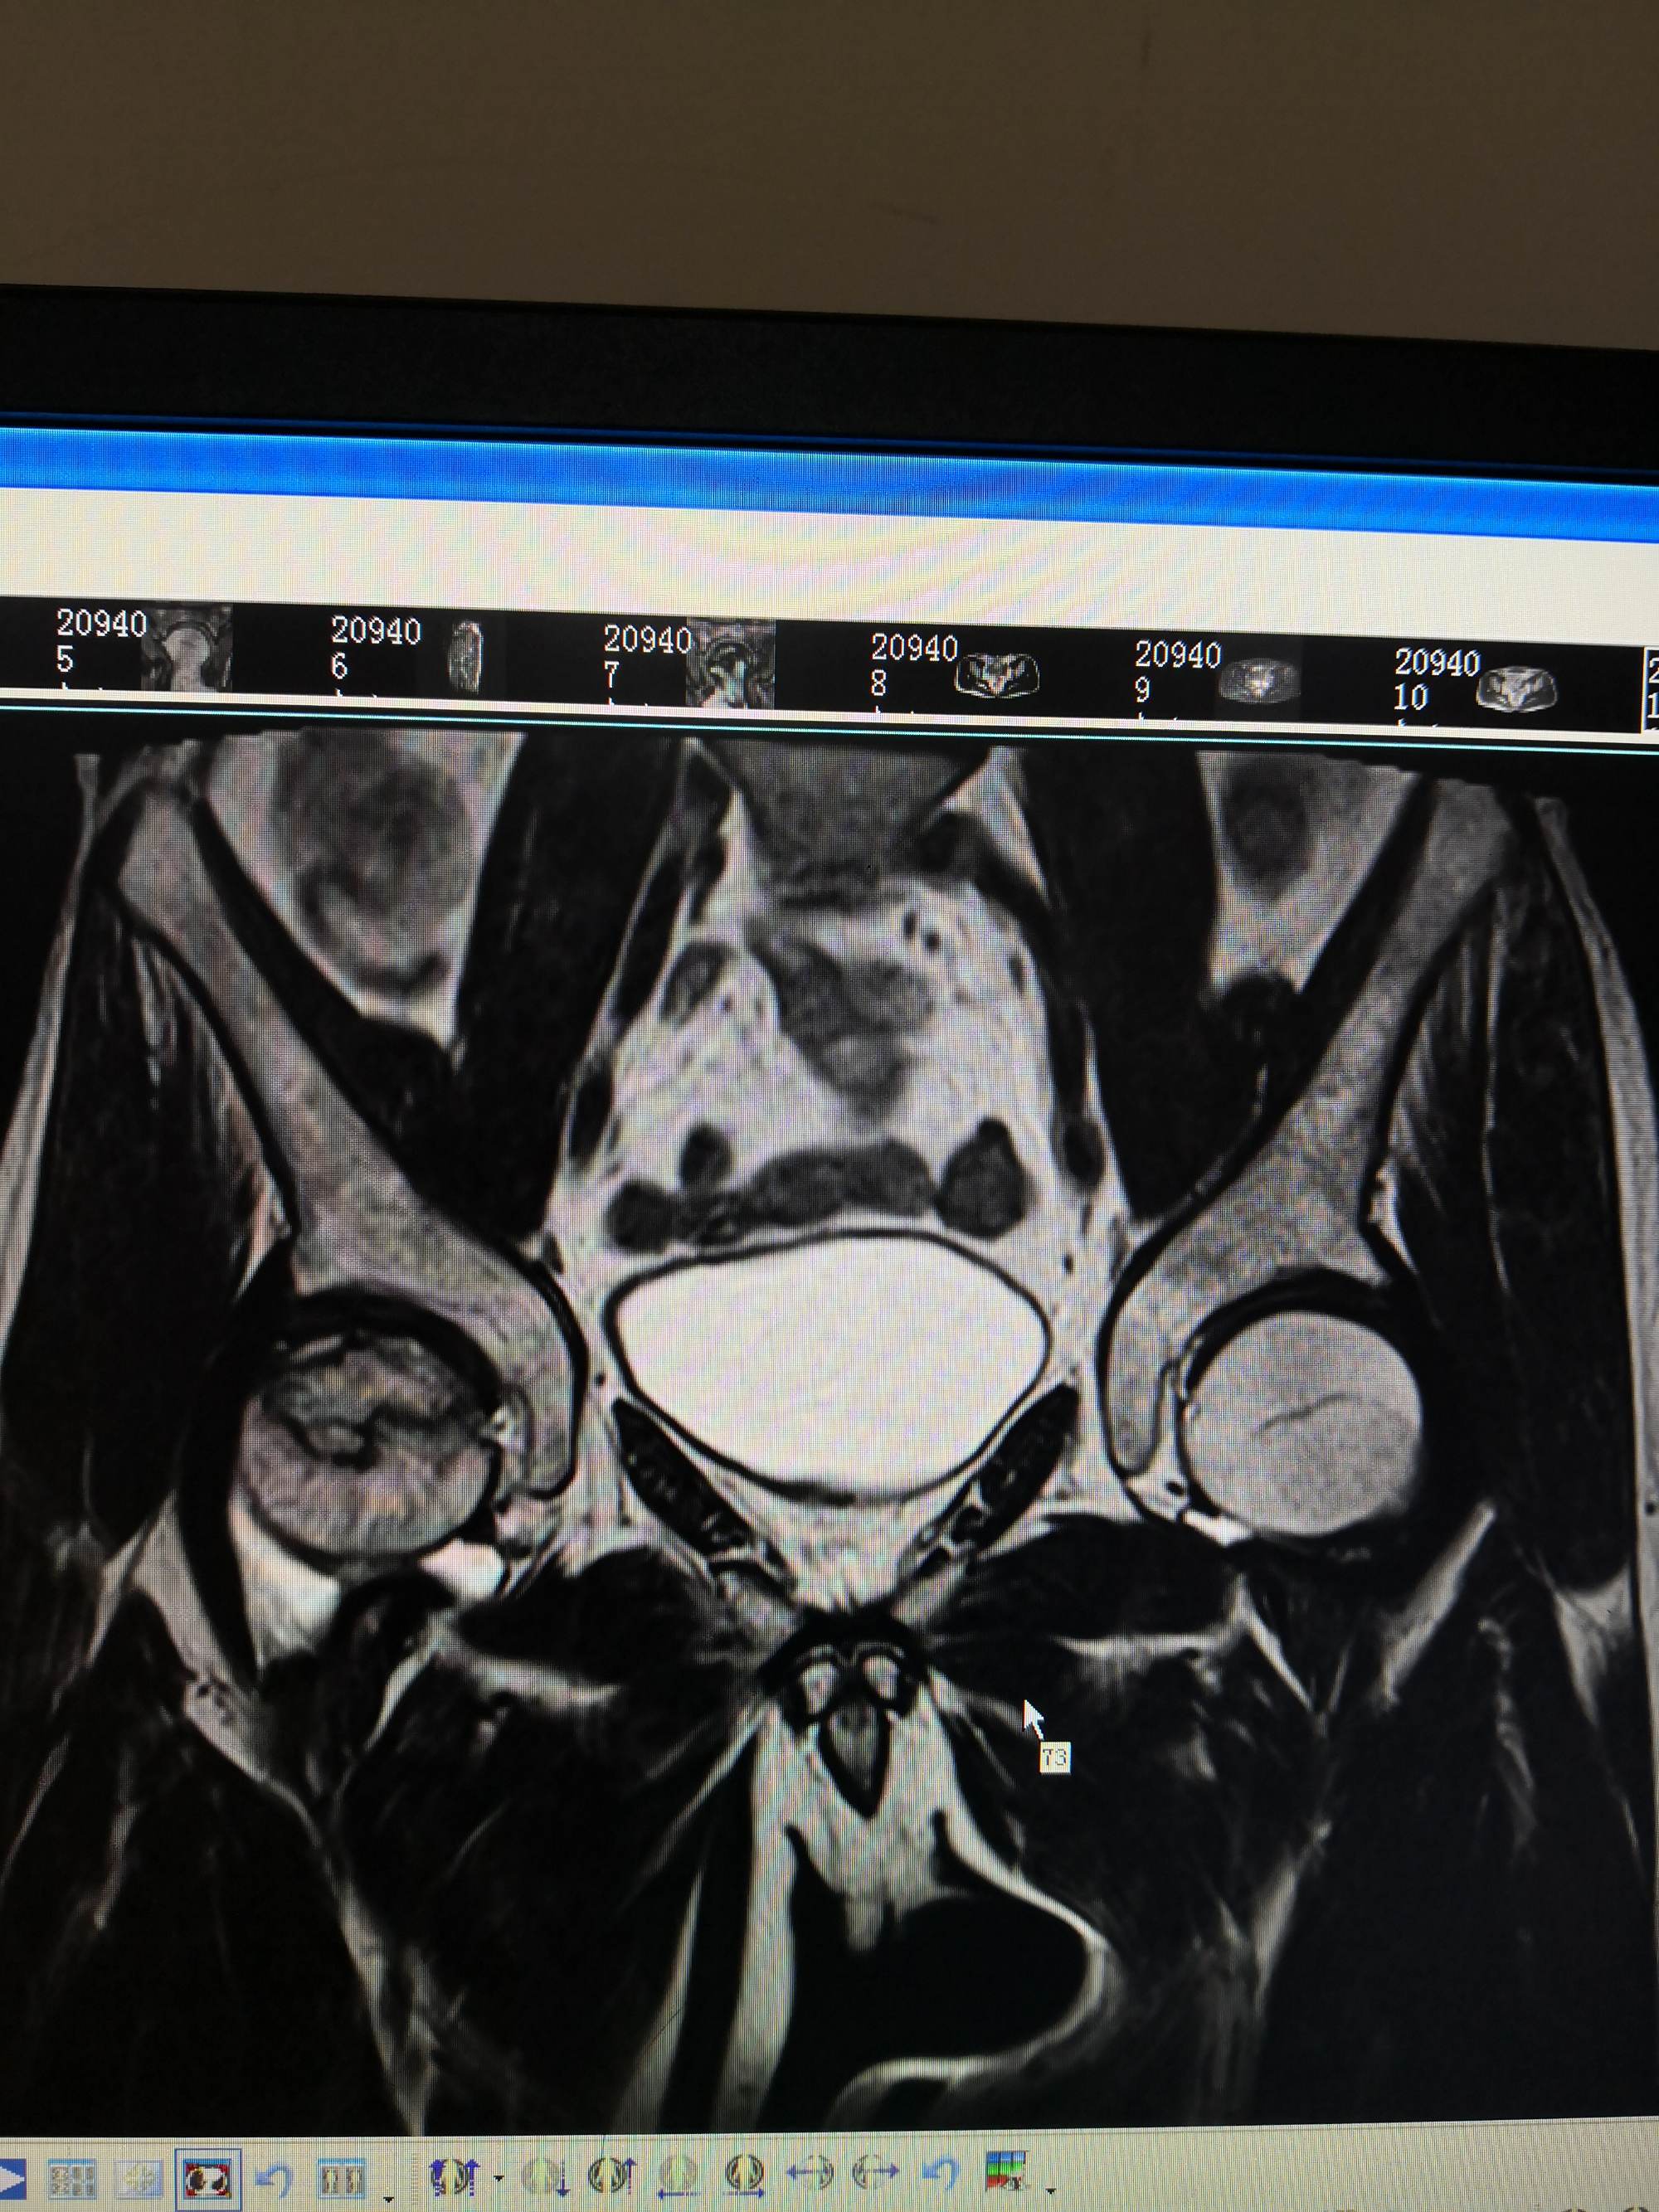

股骨头坏死(ONFH)又称缺血性股骨头坏死,是骨科中常见的难治性疾病,主要病因是股骨头血液供应遭到破坏,导致骨髓成分减少与骨细胞死亡,最终股骨头坏死塌陷,引起髋部疼痛,降低患者的生活质量。

股骨头坏死可发生在任何年龄段,我国股骨头坏死的发病率高且逐年升高。据2017年我国统计的数据显示,我国15岁及以上的普通人群中约812万人患有非创伤性骨头缺血坏死。多数患者在早中期没有采取积极措施,导致病情发展至末期,难以治疗。